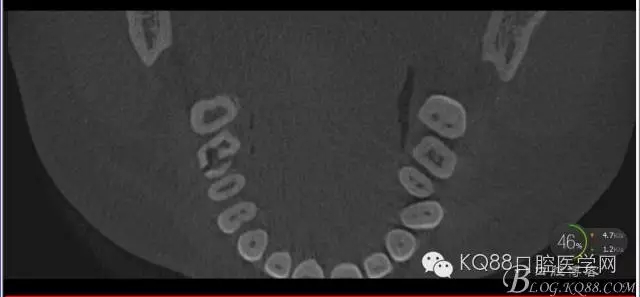

下面是拔牙后三個月的CBCT。垂直骨高度約6.7mm。

另外一個切面。垂直骨高度不夠,準(zhǔn)備 :做內(nèi)提升,植骨,植入植體。